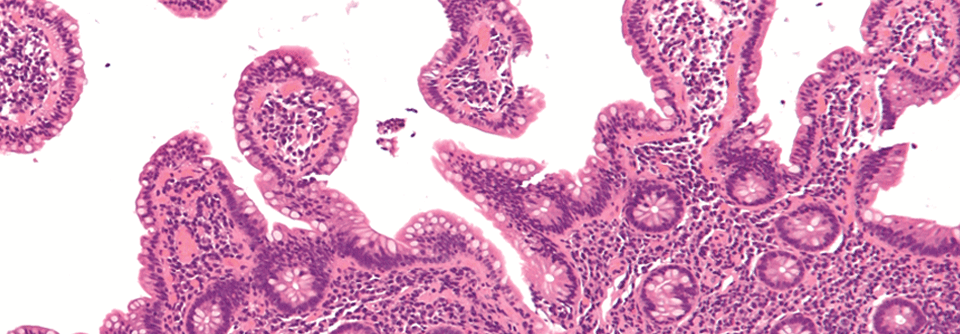

An Behandlungsmöglichkeiten mangelt es bei Lymphomen nicht. An Behandlungsmöglichkeiten mangelt es bei Lymphomen nicht. © Dr. N. Lange – stock.adobe.com

Das Therapiespektrum bei Leukämien und B-Zell-Lymphomen hat sich in den letzten Jahren deutlich erweitert. Noch fehlen zu den Neuerungen offizielle Algorithmen, welches Vorgehen für welche Patienten sinnvoll ist. Auf dem ASCO Jahreskongress gaben Experten Entscheidungshilfen.

Gentechnologie, Antikörper, Small Molecules oder Immunmodulatoren – neben der klassischen Chemotherapie stehen mittlerweile viele weitere Ansätze für die Behandlung von B-Zell-Neoplasien zur Verfügung. Das eröffnet neue Möglichkeiten, allerdings fehlen häufig noch konkrete Empfehlungen zur Verwendung dieser Präparate.